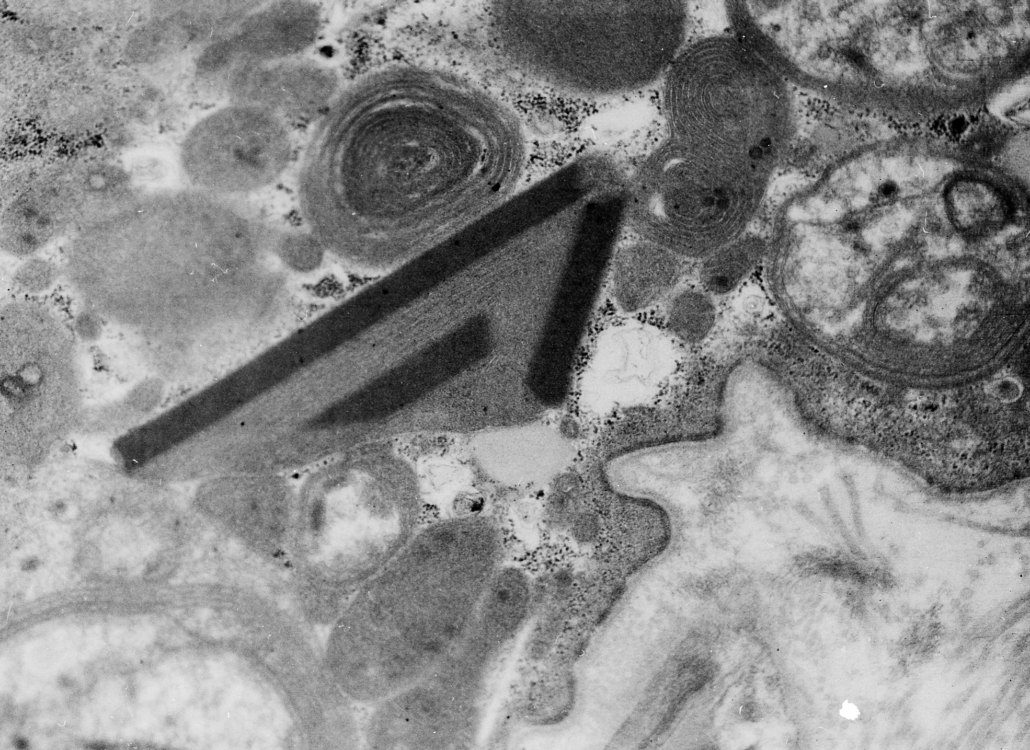

Credit photo: Anomalie mitocondriali

Tre tipi di mitocondri anomali e disfunzionali: due mitocondri con creste concentriche, uno con tre inclusioni paracristalline e uno con dimensioni aumentate, anomalie e riduzione delle creste.

Immagine acquisita mediante microscopia elettronica. Ingrandimento 7.000×.

SSD Neurologia-Malattie Neuromuscolari e rare – SC Neurologia, Fondazione IRCCS Ca’ Granda Ospedale Maggiore Policlinico, Milano. Università degli Studi di Milano.